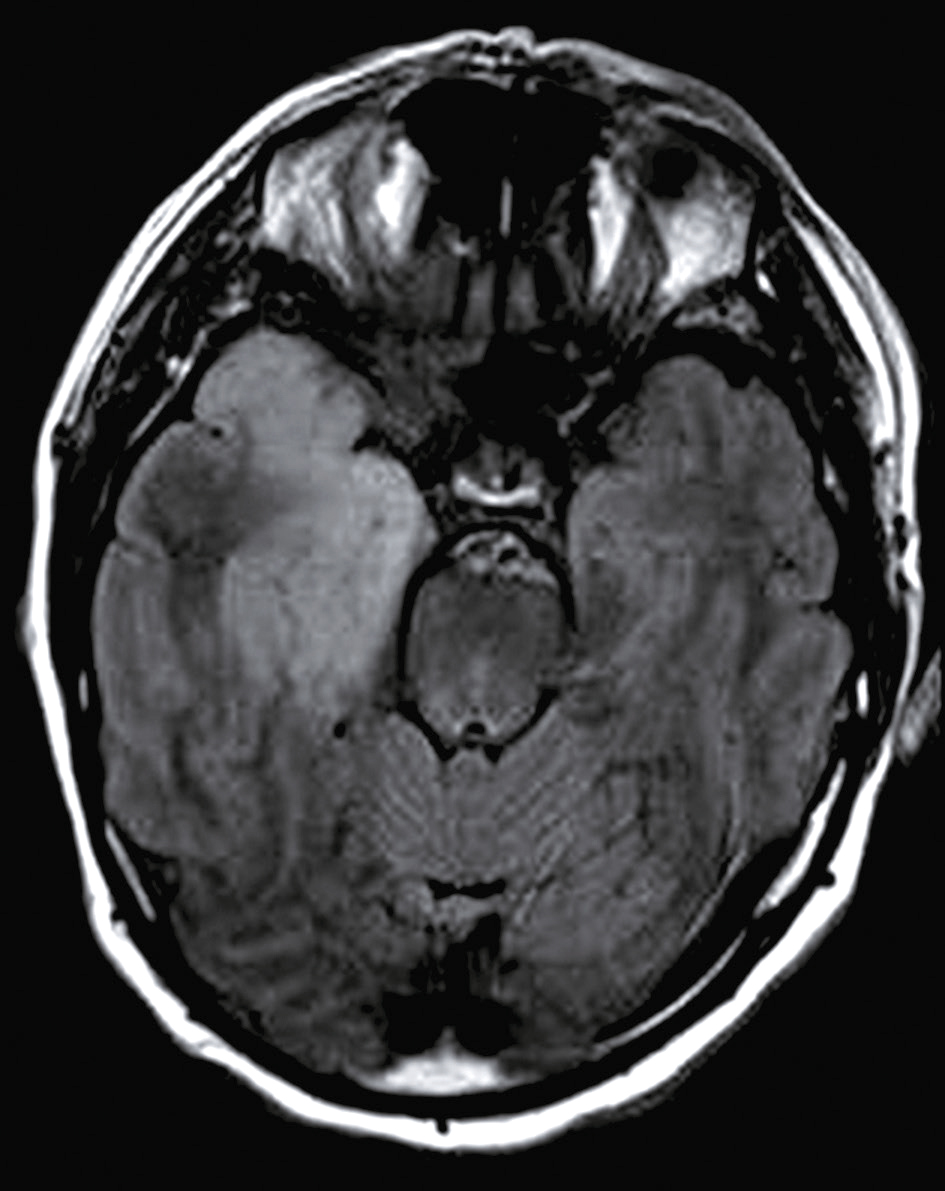

• Figure L’imagerie cérébrale peut montrer une prise de contraste méningée à la base du cerveau, des tuberculomes ou des infarctus cérébraux témoignant d’une angéite cérébrale.

L'IRM en séquence FLAIR montre des zones hyperintenses dans le lobe temporal, caractéristiques d'une méningo-encéphalite herpétique, essentielles pour le diagnostic et le traitement.

Fig. 24.5 Figure IRM cérébrale en séquence FLAIR chez un patient présentant une méningo-encéphalite herpétique.

Hypersignal franc des régions antérieure et médiale du lobe temporal droit, avec atteinte plus subtile de la région médiale du lobe temporal gauche.

L'image montre une IRM cérébrale en séquence FLAIR d'un patient présentant une méningo-encéphalite herpétique. La séquence FLAIR, ou Fluid Attenuated Inversion Recovery, est une technique d'imagerie par résonance magnétique qui permet de supprimer le signal du liquide céphalorachidien pour mieux visualiser les anomalies du parenchyme cérébral. Dans le cas de la méningo-encéphalite herpétique, une infection causée par le virus de l'herpès simplex, cette séquence est particulièrement utile pour détecter les lésions inflammatoires et les œdèmes dans le cerveau. Sur cette image, on peut observer des zones hyperintenses, c'est-à-dire des régions plus claires, qui indiquent la présence d'inflammation et de dommages au niveau du lobe temporal, une localisation typique de cette infection. La méningo-encéphalite herpétique est une condition grave qui nécessite une prise en charge rapide et appropriée pour éviter des complications sévères. L'IRM en séquence FLAIR est donc un outil diagnostique essentiel pour identifier et évaluer l'étendue des lésions cérébrales causées par cette infection. Les zones hyperintenses visibles sur l'image sont des indicateurs clés de l'inflammation, permettant aux cliniciens de mieux comprendre la gravité de la maladie et de planifier le traitement en conséquence. En résumé, cette IRM révèle des lésions inflammatoires caractéristiques de la méningo-encéphalite herpétique, offrant des informations cruciales pour le diagnostic et la gestion de cette affection.